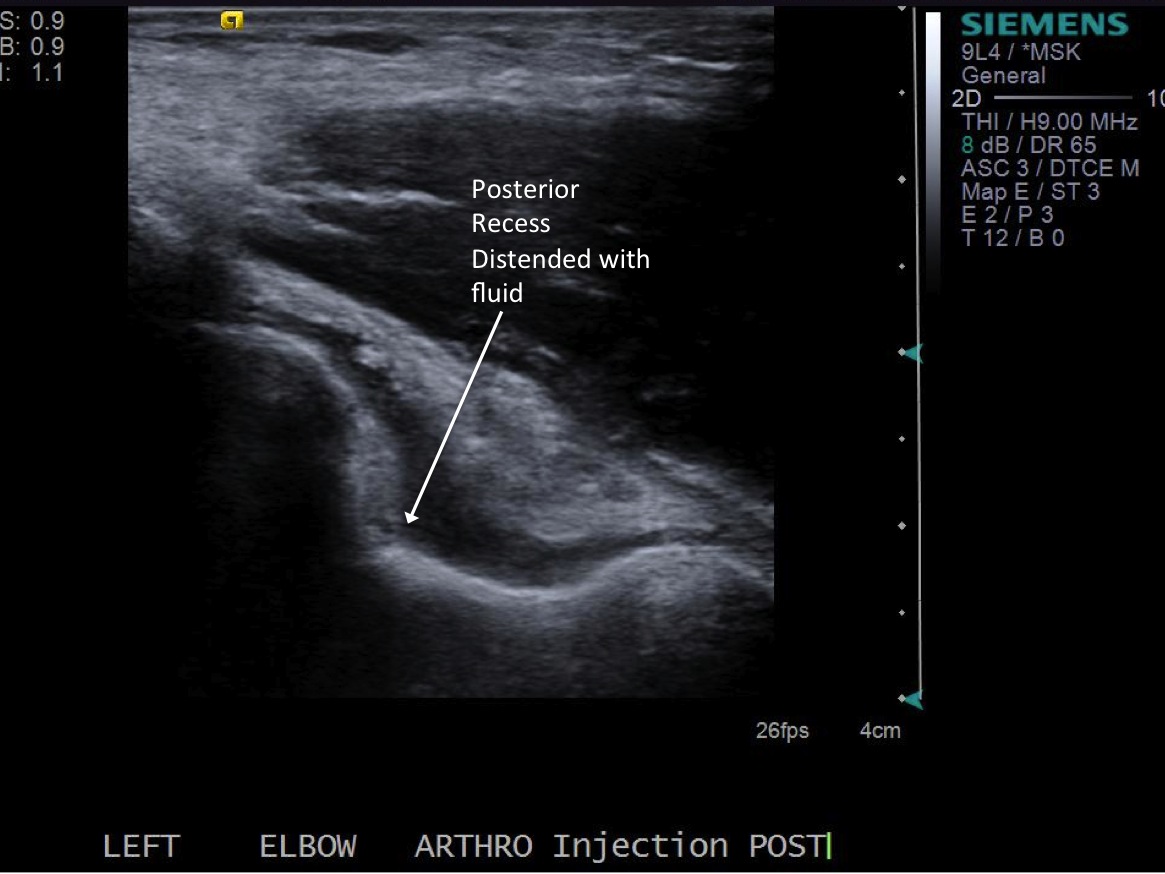

Post procedure images demonstrating distention of the joint in the posterior recess.